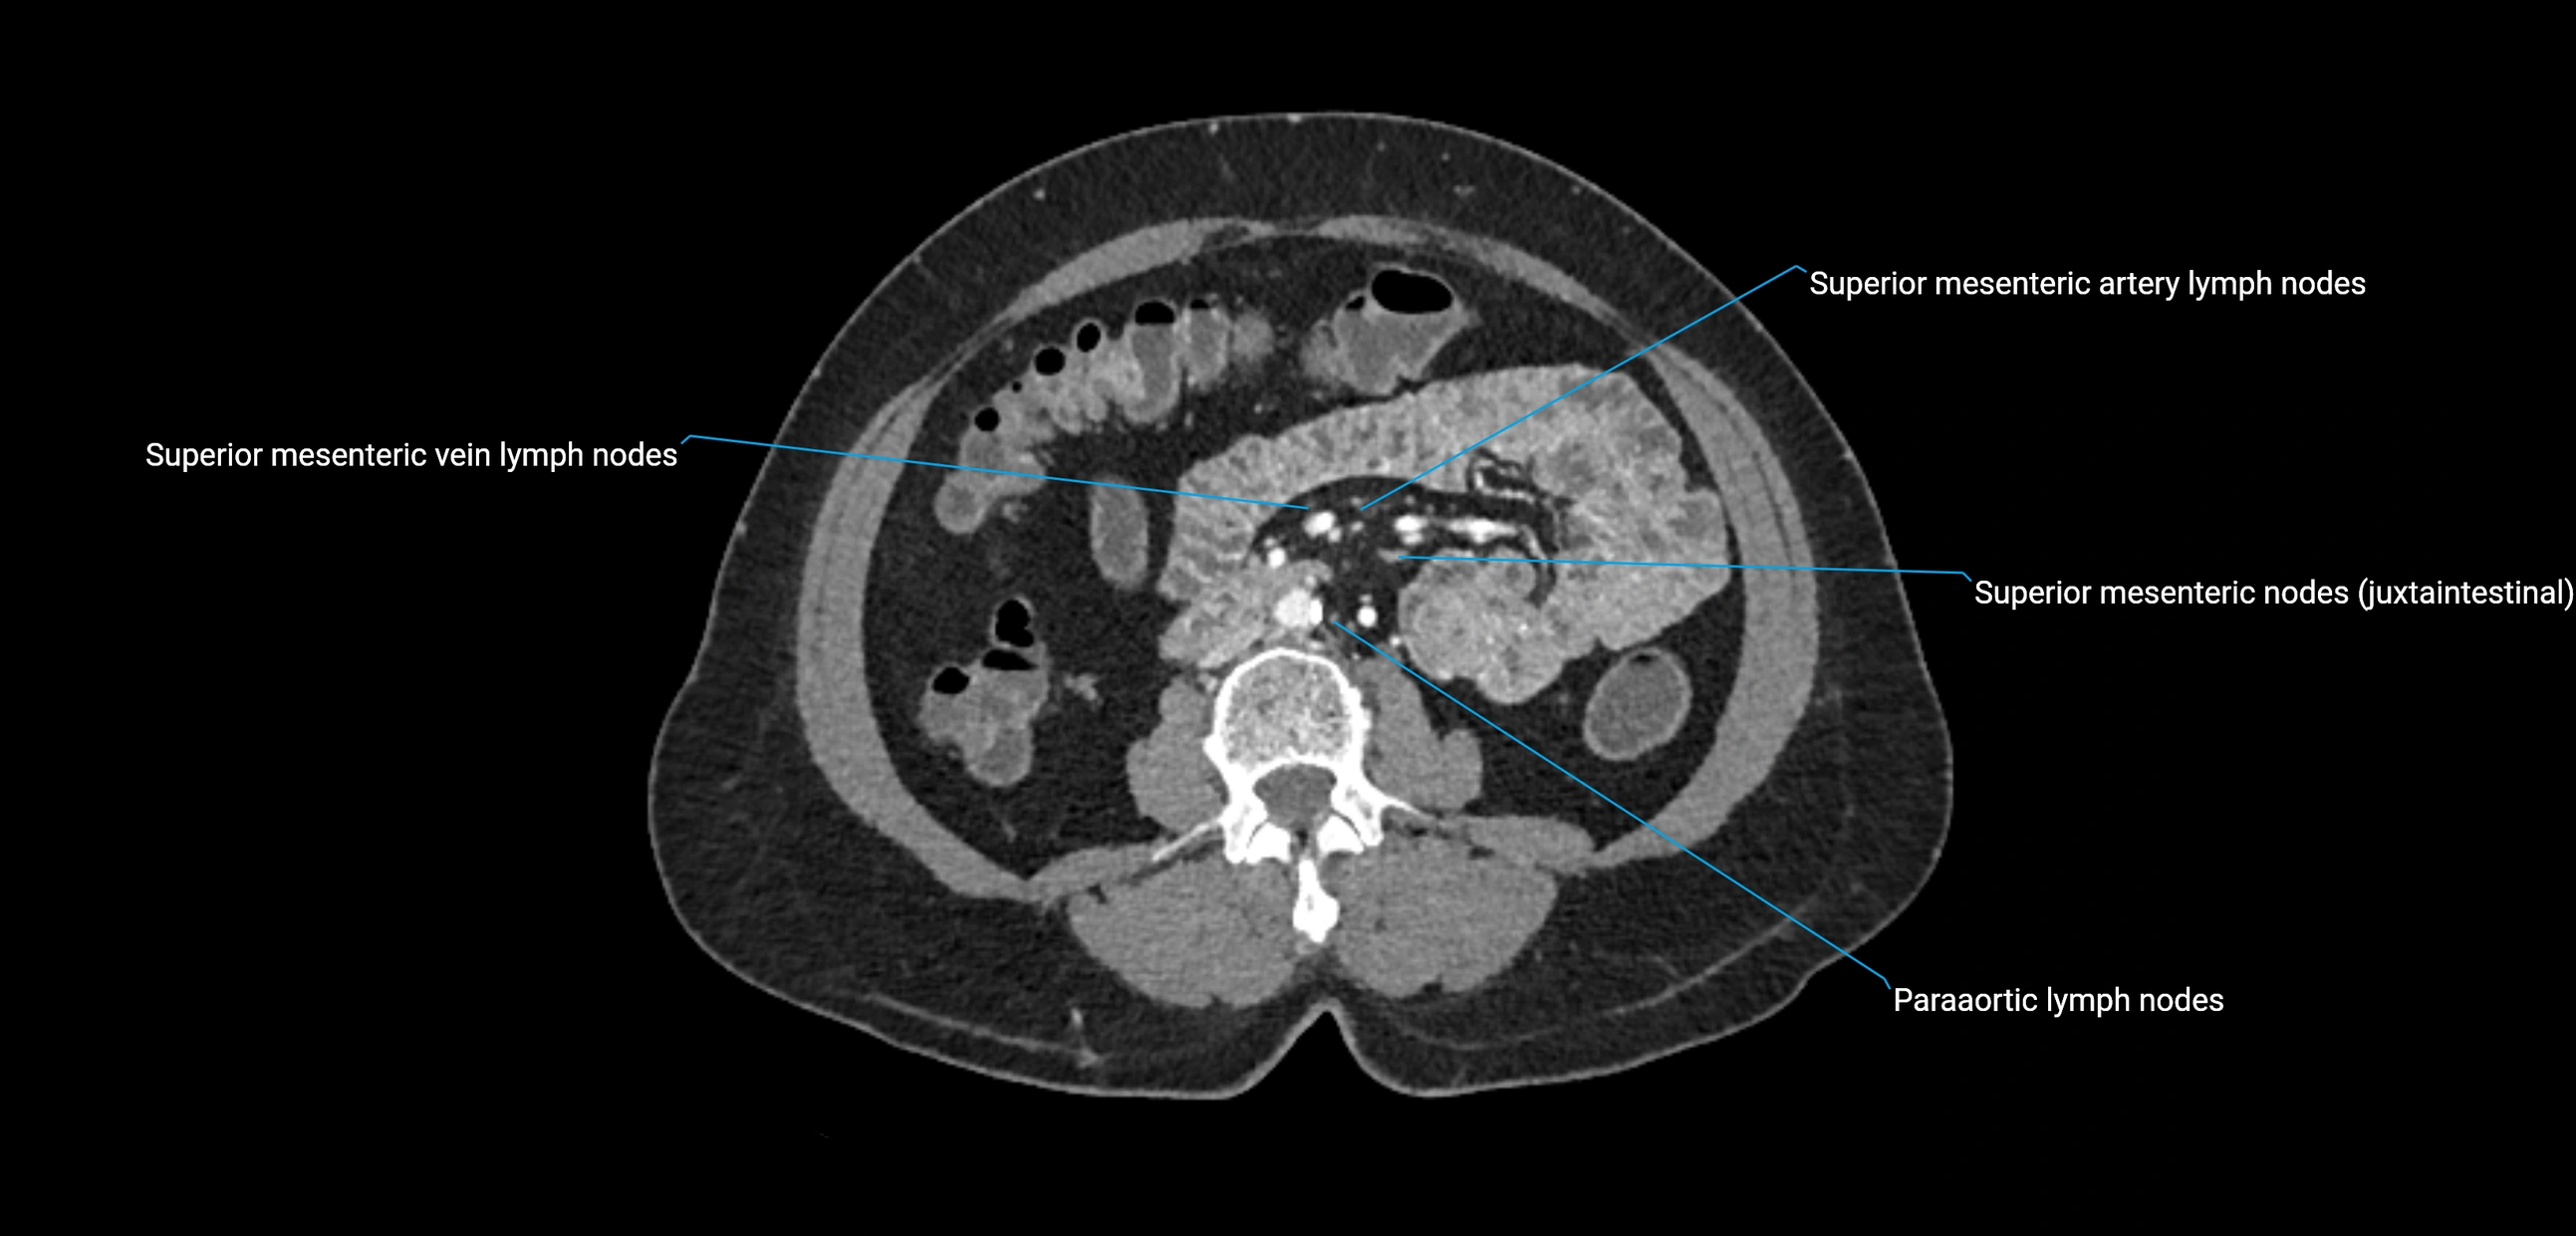

CT Appearance

CT Pre-Contrast:

• Nodes appear as soft-tissue density nodules adjacent to the aorta and IVC

• Calcification may be seen in chronic infections (e.g., tuberculosis)

CT Post-Contrast:

• Normal nodes enhance homogeneously

• Malignant nodes may show heterogeneous enhancement, central necrosis, or conglomerate formation

• Size >1 cm short axis is suspicious, though morphology and distribution are equally important

CT Venography (CTV):

• Demonstrates nodal encasement or compression of adjacent vessels (aorta, IVC, renal veins)

• Useful in staging testicular and ovarian malignancies

• Provides 3D reconstructions for retroperitoneal lymph node dissection planning